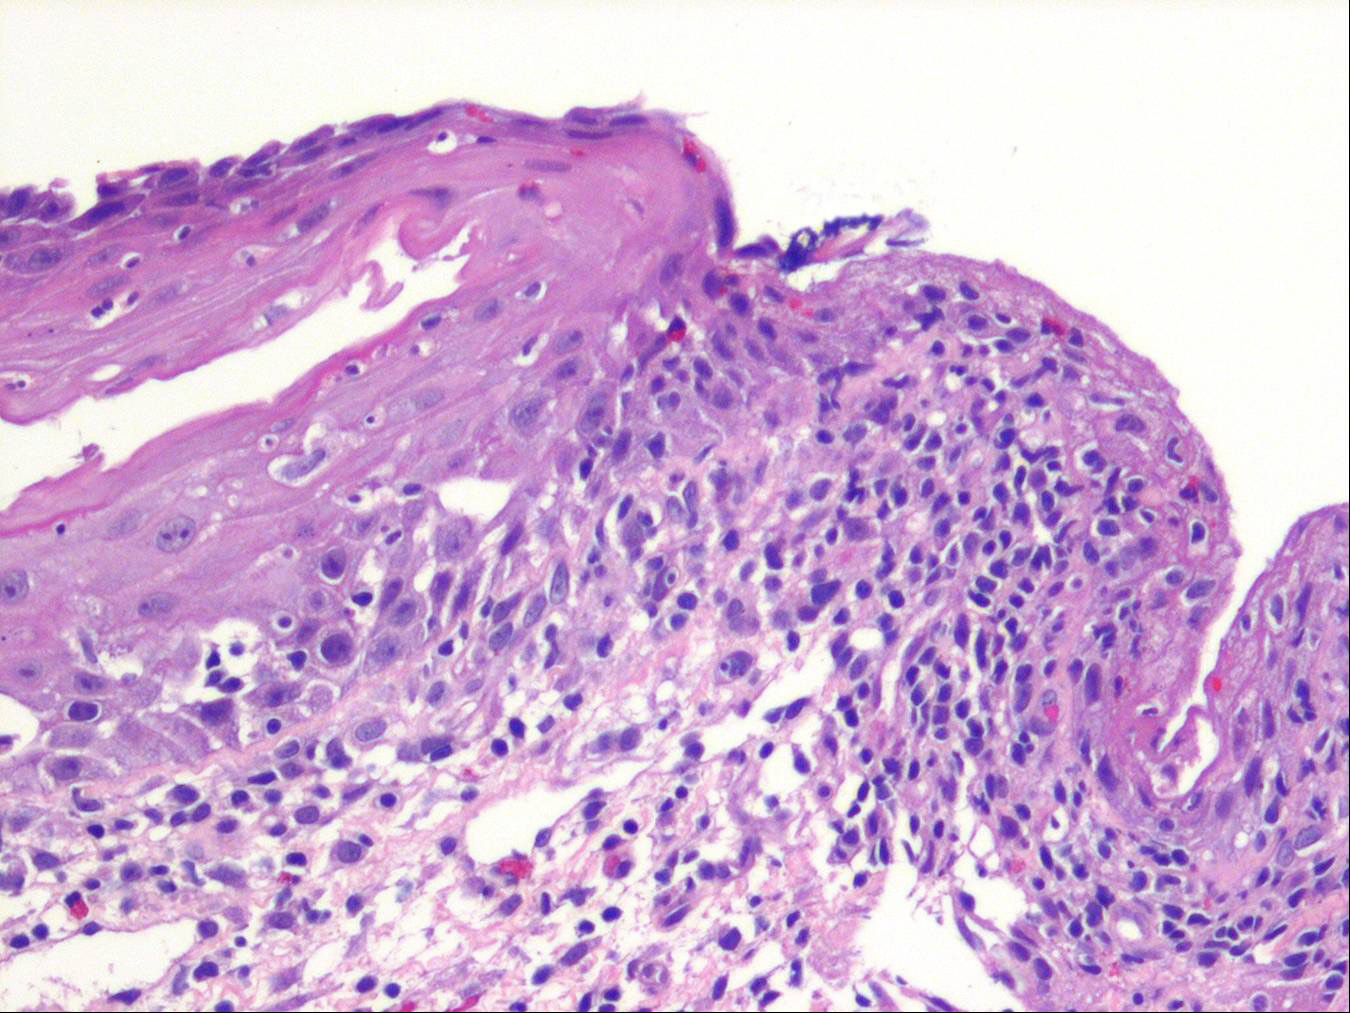

Oropharyngeal lichen planus = الحزاز المنبسط الفموي البلعومي